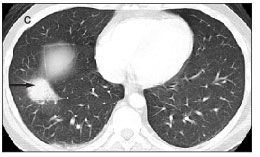

copies/mL. There was concern for ganciclovir-resistant CMV, so treatment was switched to foscarnet. He underwent video-assisted thoracoscopic surgery on hospital day 12. Histopathology showed smudge cells with viral inclusions (Figure 3). Stains were negative for CMV and herpes simplex virus. A lung tissue culture was positive for adenovirus; viral cultures of FNA material and BAL fluid also eventually grew adenovirus. His serum adenovirus DNA level (using PCR) was 1.9 × 108 copies/mL (ViraCor Laboratories, Le

Figure 3.A: Low-power view (original magnification ×200) of a hematoxylin and eosin stain of lung parenchyma with intra-alveolar proteinaceous exudate, neutrophilic infiltrate, and karyorrhectic debris. B: Medium-power view (original magnification × 400) of a hematoxylin and eosin stain of lung parenchyma with intra-alveolar proteinaceous exudate, neutrophilic infi

ltrate, karyorrhectic debris, and nuclear inclusions (smudge cells). The arrows identify smudge cells. C: High-power view (original magnification ×1000) of a hematoxylin and eosin (oil immersion) stain showing the infected cells with inclusions (smudge cells). The arrow identifies a smudge cell.

Serum adenovirus DNA levels greater than 1 × 106 copies/mL in children after allogeneic stem cell transplantation have been associated with an increased likelihood of death.23 Histopathologically, adenoviruses can cause characteristic intranuclear inclusions. Early after infection, cells may display small eosinophilic inclusions. During the later stages of infection, basophilic inclusions appear, which initially may be surrounded by a clear halo within the nucleus.31 When these intranuclear inclusions enlarge and obscure the nuclear membrane, the cells are referred to as smudge cells.2,32 Because these findings are often nonspecific, immunohistochemical or in situ hybridization techniques are used to confirm the presence of adenovirus.1